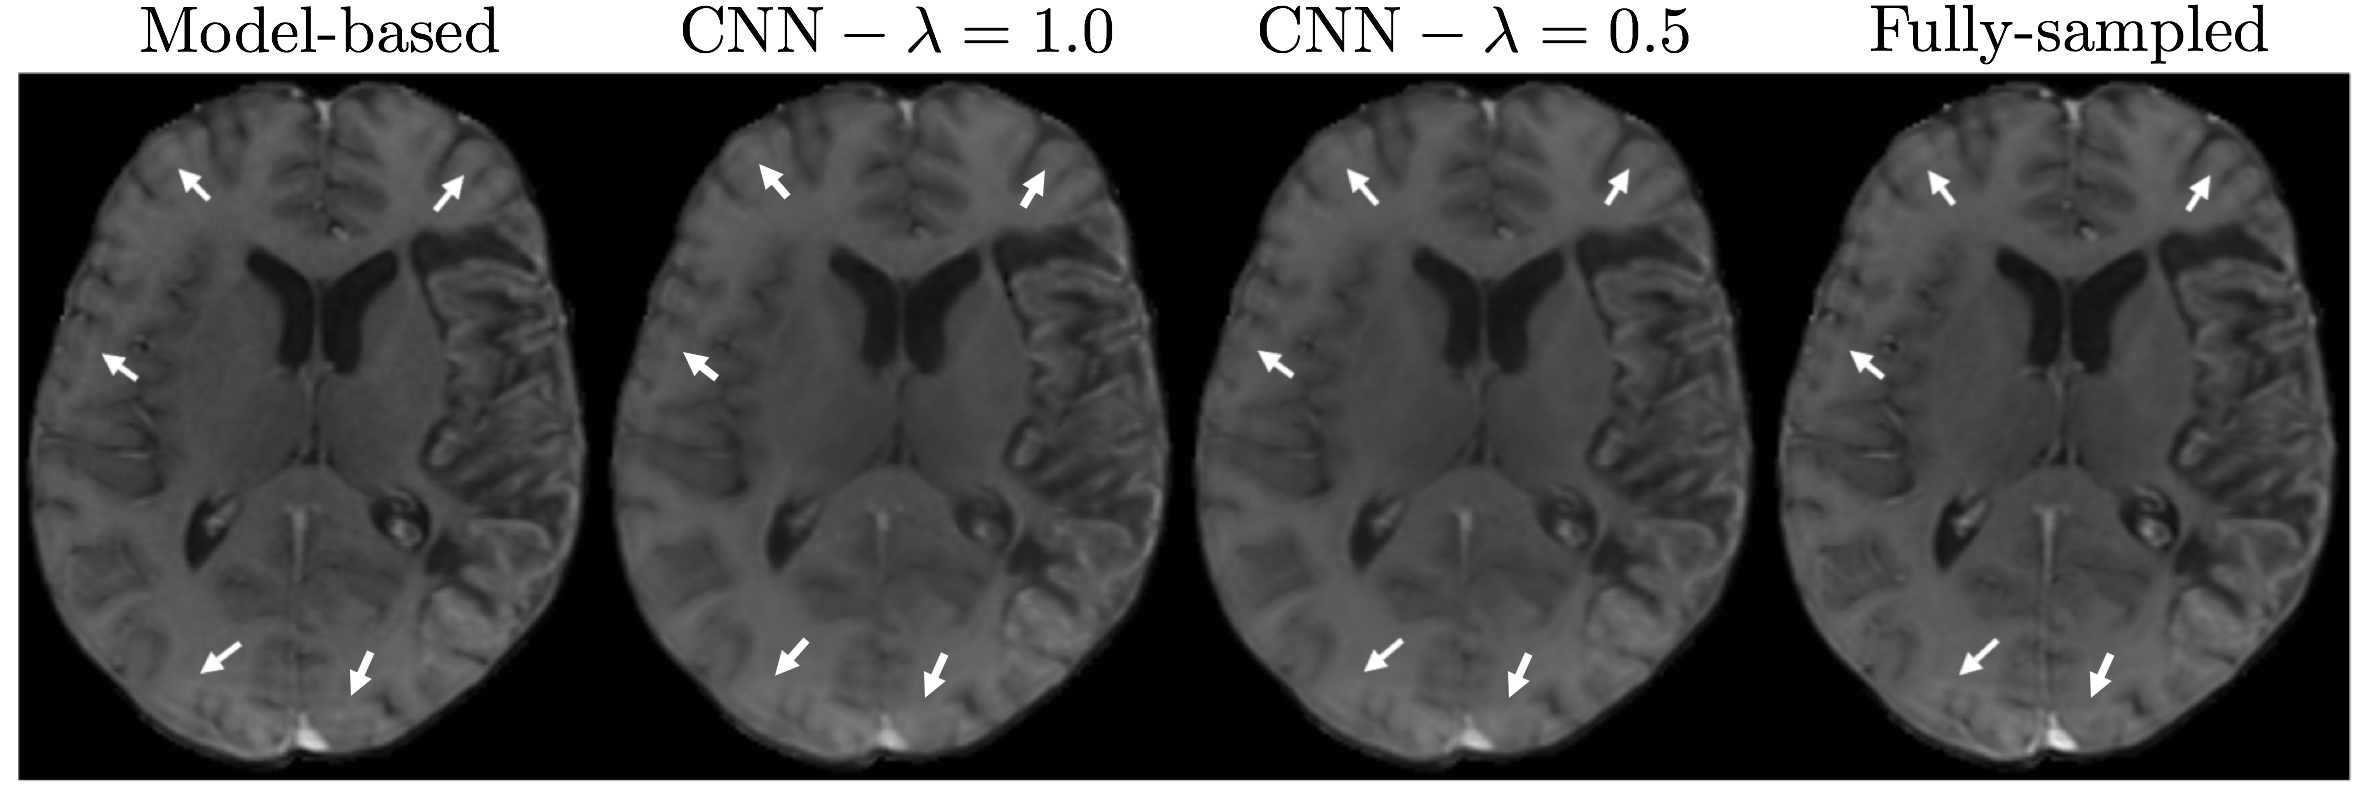

In Fig. 5 we present the exemplary reconstructed images obtained by applying the operation to the estimated PK maps. All the reconstruction approaches result in high quality images, however, the model-based reconstruction can better preserve the finer details. Unfortunately, our fully-sampled data suffer from Gibbs artifacts appearing as multiple parallel lines throughout the image. As marked by white arrows, our CNN method can significantly suppress these artifacts whereas they still appear in the image obtained by model-based iterative reconstruction. Finally, Fig. 6 demonstrates the quantitative results of parameter estimation and image reconstruction. The highest CCC and SSIM values for parameter estimation are achieved by our CNN model when both loss terms are incorporated with and , yielding an average score of 0.88 and 0.92, respectively. The difference is statistically significant for both CCC () and SSIM () when compared against model-based reconstruction. The model-based reconstruction performs the highest PSNR for image reconstruction, where it is followed by the proposed CNN with . The difference between them is statistically significant with . The PSNR also shows a decreasing trend with increasing as expected.